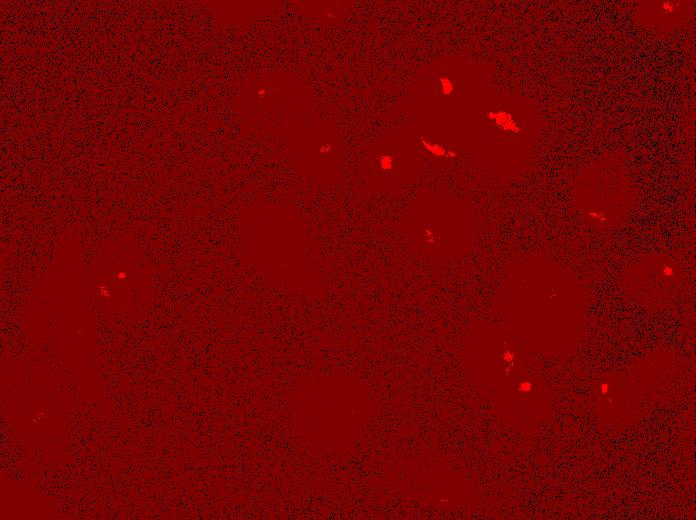

Golgi Apparatus

(anti-GM130)